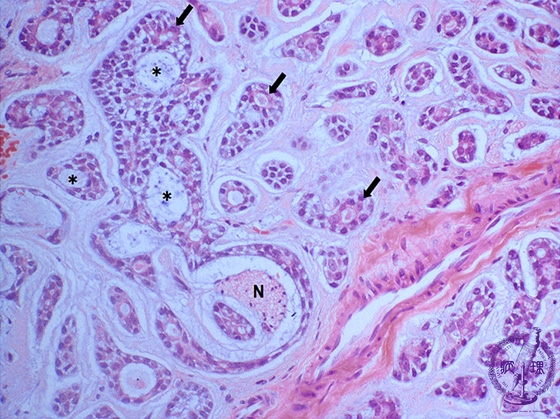

ミクロ像(HE中拡大):篩状の腔は、真の腺管(矢印)と偽嚢胞腔(*)よりなる。真の腺腔は、好酸性の細胞質を有する腺上皮細胞で囲まれ、偽嚢胞腔は細胞質に乏しい腫瘍性筋上皮/基底細胞様細胞で囲まれる。神経線維束(N)周囲への浸潤がみられる。